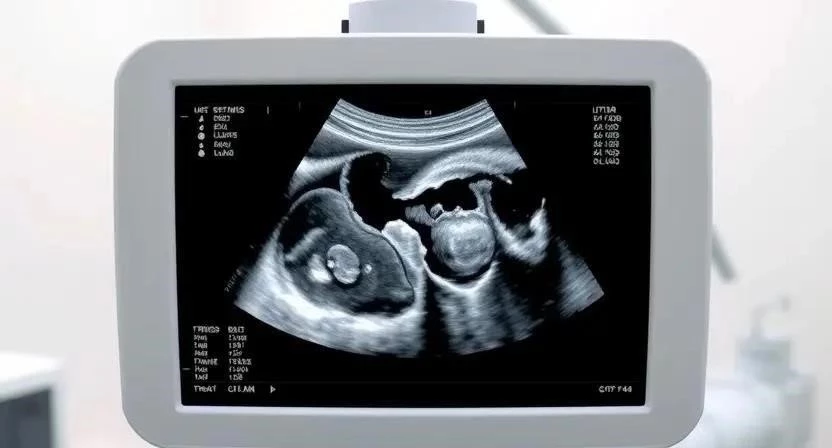

- УЗИ: Основной метод диагностики, позволяющий определить размер, расположение и количество миом.